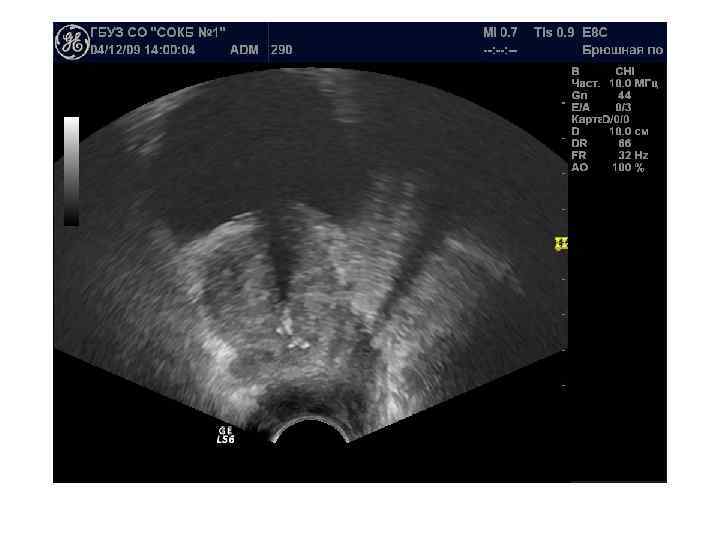

Острый простатит Острое воспалительное заболевание предстательной железы, при котором можем увидеть сонографически несколько основных признаков: - умеренное диффузное увеличение объема железы - однородность структуры железы; - наличие диффузного снижения эхогенности преимущественно в периферической части железы. - изменение семенных пузырьков в виде их асимметрии и расширение семявыбрасывающих протоков на фоне возможного блока. - умеренное расширение вен парапростатического сплетения В режиме ЦДК: симметричное и равномерное обогащение сосудистого рисунка.

Хронический простатит характеризуется полиморфизмом картины. Различают 4 формы: -отёчная – диффузное увеличение размеров и чередование зон повышенной и пониженной эхогенности с преобладанием гипоэхогенности. -конгестивная (застойная) - диффузная неоднородность структуры - чередование зон повышенной и пониженной эхогенности, отмечается более выраженная дифферецировка анатомо-функциональных зон. Размер железы может быть незначительно увеличен. -калькулёзная - присутствие гиперэхогенных включений чаще без акустической тени. -склеротическая - при которой преобладает диффузное повышение эхогенности и уменьшение размеров.